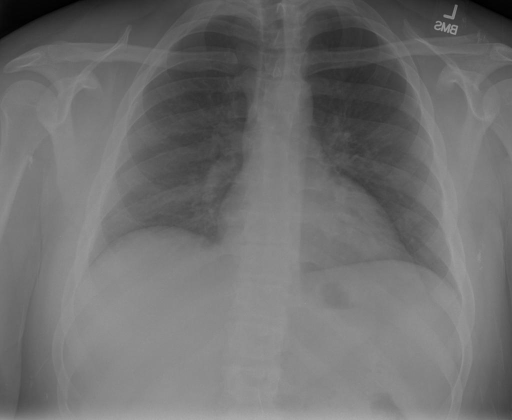

- (1)准备[诊疗报告(中文)](./data/Xray/openi-zh.json)和[X光影像](https://pan.baidu.com/s/13GBsDMKf6xBZBSHpoWH_EA?pwd=k9sh)在`data/Xray`文件夹下; - (2)开始训练: ```bash # 设置CUDA变量,主要是为了解决有时候直接训练而出现无法正确加载到显卡问题 export CUDA_VISIBLE_DEVICES=0,1,2,3 # 开始训练 bash finetune_XrayGLM.sh ``` 这里的复现过程非常简单,主要是很多过程我们都为大家准备好了,大家可以随时复现一个自己的`XrayGLM`。 ### 4.模型训练(通用) ## 效果展示 *以下效果来自于**低质量**的数据训练和权重 影像诊断: |X光影像|诊疗报告(医生)|XrayGLM| |:-|:-|:-| |![](./data/Xray/2_1.png)|根据X射线图像,心脏大小正常,肺部看起来很清晰。已经排除了肺炎、积液、水肿、气胸、腺病、结节或肿块的存在。该发现表明一切正常。换句话说,总体印象是胸部正常。|X光片显示,心脏大小正常。肺部没有气胸或胸腔积液的证据。骨骼结构看起来没有任何异常。总的来说,X光片表明没有发现急性心肺疾病的迹象。| |![](./data/Xray/2882_1.png)|X光图片显示没有扭曲的区域、可疑的骨质不透明度或胸腺积液。心脏大小轻微增大,但非常稳定。此外,没有气胸的证据,肺野也正常。总体来说,X光片显示没有急性心脏异常,但要注意轻微的心脏扩大。|X光片显示,心脏大小正常。肺部和纵隔轮廓清晰,没有气胸或胸腔积液的证据。骨骼结构完整,没有任何急性异常。| |![](./data/Xray/2577_1.png)|心影形态在正常范围内。没有急性骨质异常。有可能出现没有明显的吸水或肺实质状况的线索。没有大面积积液或气胸。有可能怀疑其有误吸或肺实质问题。为了确诊和治疗,可能需要进行适当的影像学随访。|心脏大小正常,肺部和纵隔轮廓清晰。没有急性异常或活动受限的证据。没有任何明显的气胸、胸腔积液或肺不张的迹象。此外,也没有发现任何局灶性骨质异常或其他急性疾病。| 多轮对话: |X光影像|诊疗报告(医生)| |:-|:-| |![](./data/Xray/861_1.png)|右侧主动脉突出观察到。心脏大小正常。胸部未发现明显的肺气肿、胸膜积液或可疑的肺部病变。报告指出已知右侧主动脉情况正常。| ```bash >> X光影像路径:./data/Xray/861_1.png >> 用户:这是一张什么图? >> XrayGLM:这张图片显示的是一张肺部检查的X光片。 >> 用户:请描述这张胸部X光片的诊断结果 >> XrayGLM:心脏大小正常,肺部清晰。没有急性心肺疾病的证据。 >> 用户:是否存在肺气肿? >> XrayGLM:没有肺气肿。心脏大小正常,肺部清晰。没有发现急性心肺疾病的证据。 >> 用户:平时饮食该注意什么? >> XrayGLM:饮食应该健康,均衡。建议增加蛋白质的摄入量,因为蛋白质有助于维持肌肉和骨骼的健康。多食用蔬菜、水果、全谷物以及健康的脂肪来源如橄榄油、鱼类等可以帮助获得足够的维生素和矿物质。此外,避免过度饮酒或吸烟,这些习惯可能会对心脏健康产生负面影响。 ``` ## 未来展望 1. 模型的能力更多来源于数据的支持,`OpenI-zh`作为微调数据集,其数据量足以支持研究,在更广泛的任务和性能表现上,我们认为**在大规模数据集上预训练并在高质量少量数据集上微调是一种可行的方案**; 2. 普遍意义的理解上,视觉多模态模型=视觉模型+语言模型。除了需要关注视觉模型信息与语言模型输出的搭配外,还需要**额外关注到语言模型的加强,在人机的对话中,尤其是医疗语言模型的问答上,除了专业的医疗问题回答,带有人文情怀的有温度的回答更应该是我们追寻的目标**。 ## 项目致谢 1. [VisualGLM-6B](https://github.com/THUDM/VisualGLM-6B)为我们提供了基础的代码参考和实现; 2. [MiniGPT-4](https://github.com/Vision-CAIR/MiniGPT-4)为我们这个项目提供了研发思路; 3. ChatGPT生成了高质量的中文版X光检查报告以支持XrayGLM训练; 4. [gpt_academic](https://github.com/binary-husky/gpt_academic)为文档翻译提供了多线程加速; 5. [MedCLIP](https://github.com/RyanWangZf/MedCLIP) 、[BLIP2](https://huggingface.co/docs/transformers/main/model_doc/blip-2) 、[XrayGPT](https://github.com/mbzuai-oryx/XrayGPT) 等工作也有重大的参考意义; ![](./assets/images/mpu.png) 这项工作由[澳门理工大学应用科学学院](https://www.mpu.edu.mo/esca/zh/index.php)硕士生[王荣胜](https://github.com/WangRongsheng) 、[段耀菲](https://github.com/IsBaSO4) 、[李俊蓉](https://github.com/lijunrong0815)完成,指导老师为檀韬副教授、[彭祥佑](http://www.patrickpang.net/)老师。 *特别鸣谢:[USTC-PhD Yongle Luo](https://github.com/kaixindelele) 提供了有3000美金的OpenAI账号,帮助我们完成大量的X光报告翻译工作 ## 免责声明 本项目相关资源仅供学术研究之用,严禁用于商业用途。使用涉及第三方代码的部分时,请严格遵循相应的开源协议。模型生成的内容受模型计算、随机性和量化精度损失等因素影响,本项目无法对其准确性作出保证。即使本项目模型输出符合医学事实,也不能被用作实际医学诊断的依据。对于模型输出的任何内容,本项目不承担任何法律责任,亦不对因使用相关资源和输出结果而可能产生的任何损失承担责任。 ## 项目引用 如果你使用了本项目的模型,数据或者代码,请声明引用: ```bash @misc{wang2023XrayGLM, title={XrayGLM: The first Chinese Medical Multimodal Model that Chest Radiographs Summarization}, author={Rongsheng Wang, Yaofei Duan, Junrong Li, Patrick Pang and Tao Tan}, year={2023}, publisher = {GitHub}, journal = {GitHub repository}, howpublished = {\url{https://github.com/WangRongsheng/XrayGLM}}, } ``` ## 使用许可 此存储库遵循[CC BY-NC-SA](https://creativecommons.org/licenses/by-nc-sa/4.0/) ,请参阅许可条款。